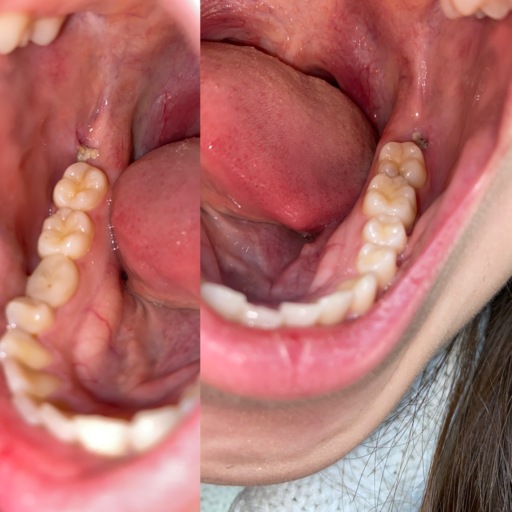

Wisdom Tooth Removal, Infection?

I got my wisdom teeth removed on January 8th (it is now Jan 23) and I'm not sure if I'm healing properly. I am unable to visit my oral surgeon again, as I attend school out of state from where I had the procedure otherwise I would go in for a quick...